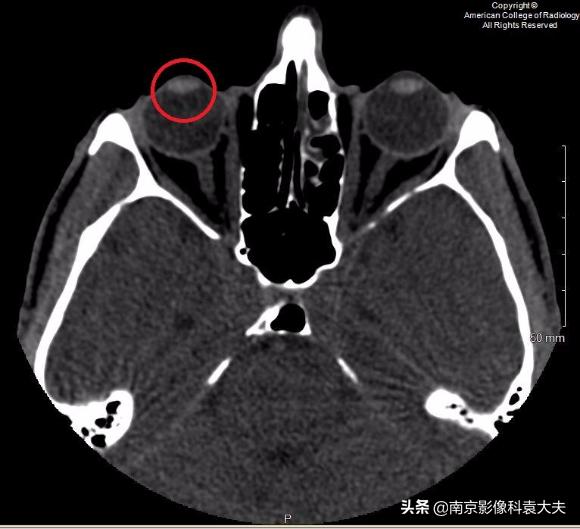

上图 在晶状体水平轴位非对比CT图像显示右眼前房(圆环)前后径减小,临床上可在角膜裂伤的情况下看到。